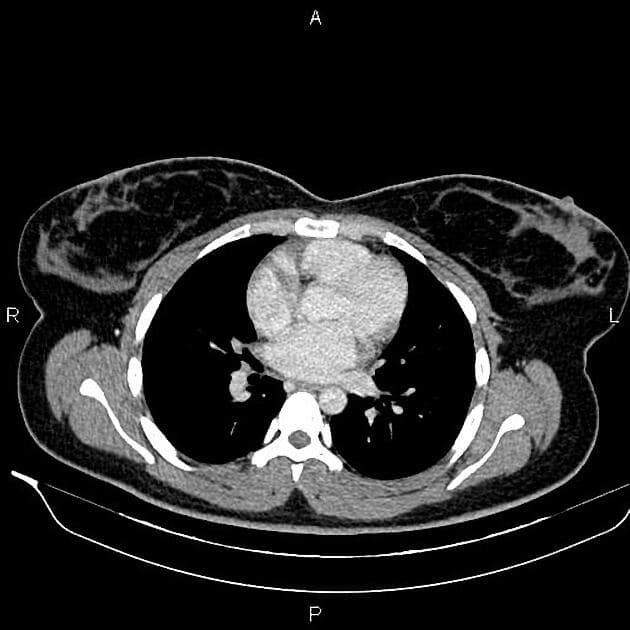

- Các nhánh đường mật trong gan (intrahepatic biliary radicles) giãn nhẹ.

- Ống mật chủ (common bile duct) giãn, thấy nhiều viên sỏi nhỏ có tín hiệu thấp ở đoạn cuối.

- Túi mật (gallbladder) căng giãn, chứa nhiều viên sỏi nhỏ.

- Tụy (pancreas) to lan tỏa và phù nề, xung quanh có dịch quanh tụy lan dọc theo các khe mỡ vùng sau phúc mạc, rõ hơn ở phía bên trái.

- Ống tụy (pancreatic duct) có vị trí, chiều dài và đường kính bình thường, cấu trúc bên trong đồng nhất, bờ trơn đều.

Sỏi túi mật (cholelithiasis) và sỏi ống mật chủ (choledocholithiasis) là những nguyên nhân phổ biến gây viêm tụy cấp (acute pancreatitis). Trong trường hợp này, viêm tụy cấp được phát hiện trên hình ảnh cộng hưởng từ đường mật tụy (MRCP) được thực hiện do có triệu chứng vàng da tắc mật và đau vùng thượng vị.

Viêm tụy cấp là một tình trạng lâm sàng phổ biến, thường do sỏi mật gây ra, đặc biệt khi chúng làm tắc ống mật chủ tại nhú tá lớn (ampulla of Vater). Trường hợp này cho thấy các hình ảnh điển hình trên MRCP bao gồm to toàn bộ tụy, dịch quanh tụy và dấu hiệu tắc nghẽn đường mật do sỏi ống mật chủ. Sự hiện diện của nhiều viên sỏi nhỏ ở đoạn cuối ống mật chủ xác nhận nguyên nhân bệnh. Chẩn đoán sớm bằng MRCP cho phép xử trí kịp thời, bao gồm nội soi mật tụy ngược dòng (ERCP) để lấy sỏi. Việc phân biệt viêm tụy cấp với các nguyên nhân khác gây đau bụng và vàng da như viêm đường mật hay ung thư tụy là rất quan trọng vì các bệnh này đòi hỏi can thiệp khác nhau.